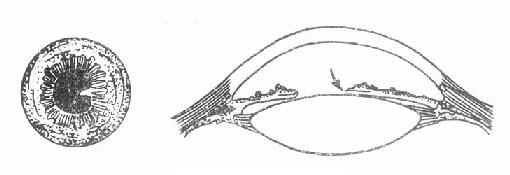

(3)角膜后沉降物(keratic precipitates):简称KP,房水中的细胞和色素,受温差的影响沉淀于角膜内皮后表面,在下半部构成三角形排列,即KP。由于炎症的性质不同,KP的形态各异,由嗜中性白细胞形成时呈白色尘埃状;由淋巴和浆细胞组成时呈白色小点状;由上皮样细胞构成时,呈灰白色油腻状,称为羊脂状KP。前两种多见于急性虹膜睫状体炎,后者多见于晶体皮质过敏性葡萄膜炎或交感性眼炎。新鲜时常为灰白色,陈旧时因附有色素呈棕色。(图8-1)

图8-1 角膜后沉降物